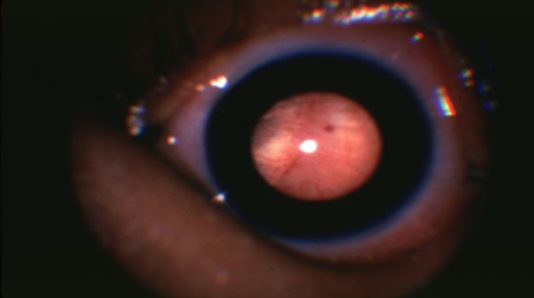

melanocytosis/uveal melanoma

melanocytosis/uveal melanoma